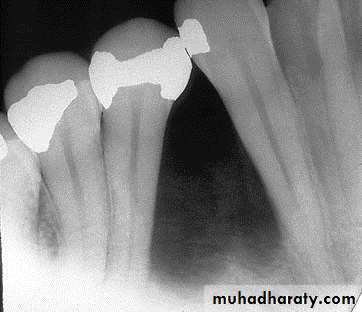

Cementoblastoma

_ True neoplasm of cementoblasts_ First mandibular molars

_ Cortex expanded without pain

_ Involved tooth ankylosed

Radiology: apical mass radiolucent halo with dense lesions